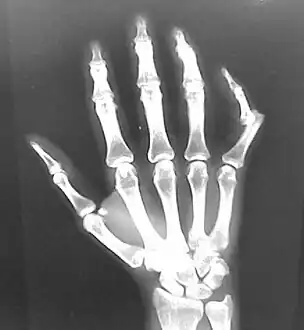

- Finger: Interphalangeal (IP) or metacarpophalangeal (MCP) joint dislocations[31]

Dislocation of the left index finger

Radiograph of left index finger dislocation

Dislocation of the carpo-metacarpal joint.